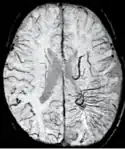

An SWI venogram of a neonate with Sturge–Weber syndrome who did not display neurological symptoms is shown to the right. The initial conventional MR imaging methods did not demonstrate any abnormality. The abnormal venous vasculature in the left occipital lobe extending between the posterior horn of the ventricle and the cortical surface is clearly visible in the venogram. Due to the high resolution even collaterals can be resolved.